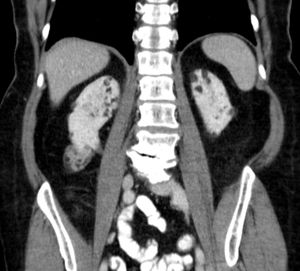

4. 3. 신장 증상

결절성 경화증 환자의 26%에서 80%는 혈관근지방종이라고 불리는 신장의 양성 종양을 가지고 있으며, 혈뇨가 가장 흔한 증상이다.[6] 결절성 경화증 혈관근지방종은 발병 연령(31.5세 vs 53.6세), 평균 종양 크기(8.2cm vs 4.5cm), 수술적 중재가 필요한 사례의 비율(50% vs 28%)에서 결절성 경화증이 아닌 혈관근지방종과 다르다.[6] 양성 종양이지만 4cm보다 큰 혈관근지방종은 자연적으로 또는 경미한 외상으로 잠재적으로 치명적인 출혈의 위험이 있다.

뇌 MRI를 통해 뇌 결절, 뇌실막하 결절, 뇌실막하 거대세포 별아교세포종 등을 확인할 수 있다.[21] 뇌파 검사(EEG)를 통해서는 뇌전증 여부를 확인하고, 발작 유형을 평가한다.[21] 복부 CT 또는 MRI를 통해 신장 혈관근지방종, 신장 낭종 등을 확인할 수 있다.[6] 고해상도 흉부 CT (HRCT)를 통해 폐 림프관평활근종증 여부를 확인할 수 있는데, 이는 주로 성인 여성에게서 나타난다.[7] 심장 초음파 검사를 통해서는 심장 횡문근종 여부를 확인할 수 있으며, 주로 영유아에게서 발견된다.[8] 안과 검진을 통해서는 망막 과오종 등을 확인할 수 있고[10], 피부과 진찰을 통해서는 피부 병변을 확인한다.[21]

결절성 경화증 환자의 26%에서 80%는 혈관근종이라고 불리는 신장의 양성 종양을 가지고 있으며, 혈뇨가 가장 흔한 증상이다.[6] 결절성 경화증 혈관근종은 발병 연령(31.5세 vs 53.6세), 평균 종양 크기(8.2cm vs 4.5cm), 수술적 중재가 필요한 사례의 비율(50% vs 28%)에서 결절성 경화증이 아닌 혈관근종과 다르다.[6] 양성 종양이지만 4cm보다 큰 혈관근종은 자연적으로 또는 경미한 외상으로 잠재적으로 치명적인 출혈의 위험이 있다.

mTOR 억제제는 종양 크기를 줄이고 출혈 위험을 감소시킨다. 출혈이 있는 경우, 색전술을 통해 혈관을 막아 지혈한다. 신장 절제술은 가급적 피해야 한다. 양성 신장 종양(AML)에는 외과적 절제나 에베로리무스(상품명 아피니토르)를 사용한다.

- 평생 동안 1~3년마다 복부 MRI를 반복한다. 매년 신장 기능을 확인한다. 혈관근종 출혈이 있는 경우, 색전술과 코르티코스테로이드로 가장 잘 치료된다. 신장 제거(신절제술)는 피해야 한다. 3cm보다 크게 성장하는 무증상 혈관근종은 mTOR 억제제 약물로 가장 잘 치료된다. 영상 검사에서 발견된 기타 신장 합병증에는 다낭성 신장 질환 및 신세포암이 있다.